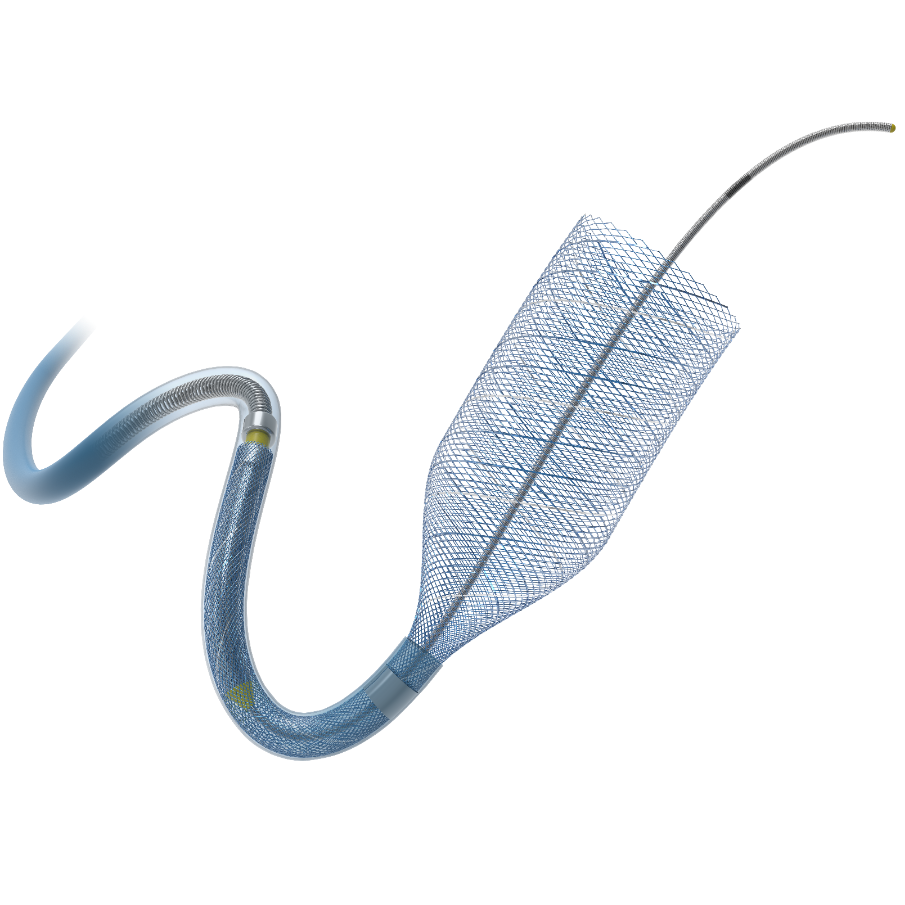

泰杰Nuva®血流导向密网支架TJED-D-6.5-40

图径下,导丝先行,在瘤内成袢进入瘤体上方血管,支架微导管在微导丝的引导下超选置于右侧大脑中动脉分叉处,建立通路后,沿着支架微导管输送Nuva®血流导向密网支架TJED-D-6.5-40顺利到位。计划支架远端定位在右侧眼动脉下方,近端定位在右侧颈内动脉岩部。

将输送系统和支架微导管整体回撤至瘤体近端正常血管,并进行原位释放。

支架完全释放后,造影显示瘤体近端血管处支架打开不良,跟进远端通路导管,微导丝塑型后进行弓背按摩。

导丝按摩后再次造影显示:支架打开显影良好,动脉瘤腔内造影剂明显滞留。撤出支架微导管后行Dyna—CT显示支架覆盖贴壁良好。